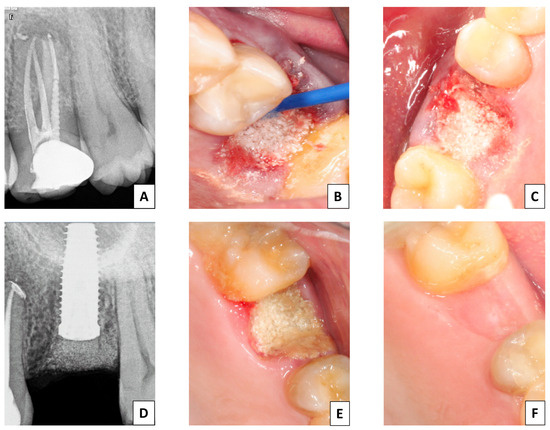

2.3.2. Surgical Procedure